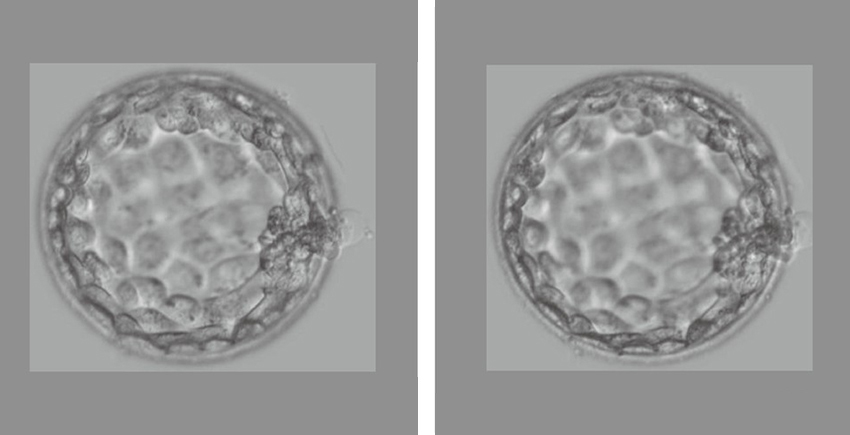

试管婴儿技术自1978年首次成功应用以来,已帮助全球数百万家庭,但成功率随年龄增长显著下降。数据显示,35岁以下女性试管婴儿成功率约为40%-45%,而40岁以上女性则降至15%以下。对于像巴斯这样选择代孕的同性伴侣,挑战更加复杂,需要协调卵子捐赠者、精子提供者和代孕母亲多方面的因素。

巴斯和特金在流产后的决定尤为感人——他们找到了第十位卵子捐赠者,并计划年内再次尝试试管婴儿。这种坚持体现了许多经历生育挑战家庭的韧性。北京大学科学家的一项突破可能为这样的家庭带来新希望:通过极体单细胞基因组测序技术,试管婴儿活产率有望从30%提高到60%

这项技术由北大第三医院乔杰教授团队开发,能更准确地诊断胚胎的遗传状况,从而选择最健康的胚胎进行移植。乔杰教授指出:“不孕不育问题困扰着高达10%-15%的育龄夫妇,而体外受精技术是解决不孕不育问题的重要方法之一。”